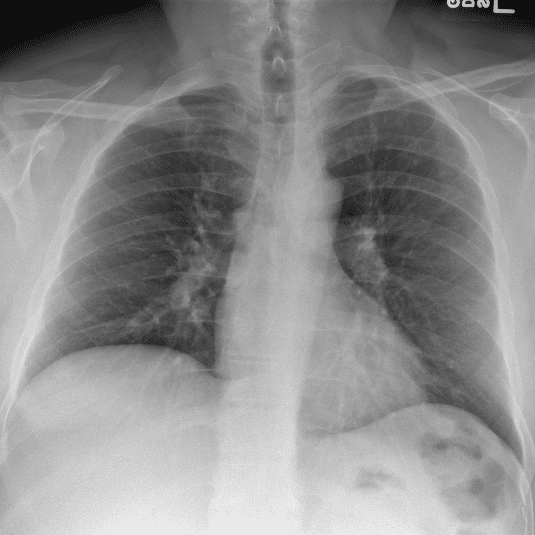

Practice Cases